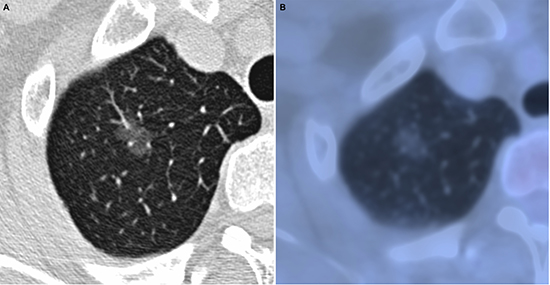

Figure 1: Adenocarcinoma in situ in 52-year-old woman. (A) transverse lung-window HRCT scan demonstrates an oval, smooth, well-defined subpleural pure GGN in the apical segment of right upper lobe. (B) PET/CT fusion image shows a 12.2-mm pure GGN with no solid component and 0.67 of SUVmax.